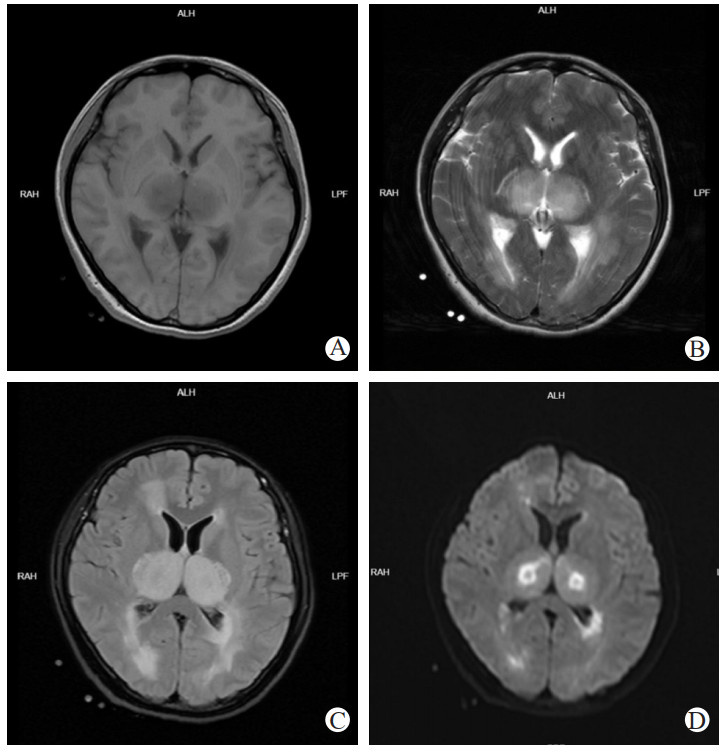

患者,青年女性,31岁,因“发热20 h意识模糊4 h”于2024-03-21 16:34入院治疗。20 h前患者出现咳嗽、头痛等上呼吸道感染症状,伴发热,最高体温为37.4 ℃。4 h前于工作期间出现意识模糊,于医院就诊,就诊期间患者神志清,后再次出现意识模糊,体温40.1 ℃。入院查体:体温39.5℃,GCS评分E4V1M5=10分,神经系统查体无阳性体征。辅助检查:血常规:超敏C反应蛋白2.26 mg/L,白细胞计数7.02×109/L,中性粒细胞比例66.4%,血红蛋白133 g/L,血小板计数196×109/L;急诊乳酸测定:乳酸5.20 mmol/L;肝肾功能:丙氨酸氨基转移酶32 IU/L,天门冬氨酸氨基转移酶26 IU/L;肌酐99.9 μmol/L。颅脑CT:未见明显异常(图 1)。初步诊断:病毒性脑炎。予以更昔洛韦针0.25 g ivgtt bid、奥司他韦75 mg bid抗病毒,地塞米松针10 mg ivgtt once抗炎治疗

注:A、B为颅脑CT影像,脑CT平扫未见明显异常;C、D为胸部CT影像,左肺下叶微小结节,建议年度复查 图 1 3月21日患者颅脑、胸部 CT

由检验结果得知,脑脊液NGS提示结核分枝杆菌复合群,但为序列2,且患者脑脊液澄清,静置后无薄膜出现,脑脊液生化提示腺苷脱氨酶为正常范围,糖及氯化物无下降,结合患者发病过程,不支持结核性中枢神经系统感染;患者咽拭子培养结果提示乙型流感病毒核酸阳性,同时对比患者3月21日以及3月22日的肺部CT影像可以看出患者肺炎进展迅猛,考虑患者乙型流感病毒感染,病因符合ANE的病因学依据。